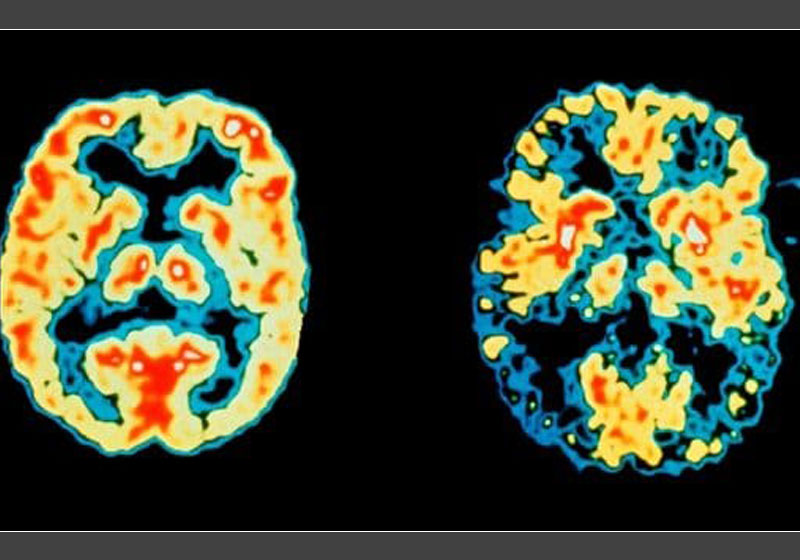

Cientistas dos EUA transformaram gene de Alzheimer em gene saudável, usando técnicas revolucionárias que “cortam” o DNA.

O estudo mostrou que é possível reverter a doença de Alzheimer com essa terapia genética.

Os pesquisadores do Instituto de Tecnologia de Massachusetts descobriram o gene que provoca o acúmulo de proteínas beta-amilóides – que entopem o cérebro – pode ser inofensivo com um “recorte” genético.

Em experimentos usando células de paciente com demência, a variante do gene defeituoso APOE4 foi transformada na versão APOE3 saudável, usando a técnica, conhecida como edição genética.